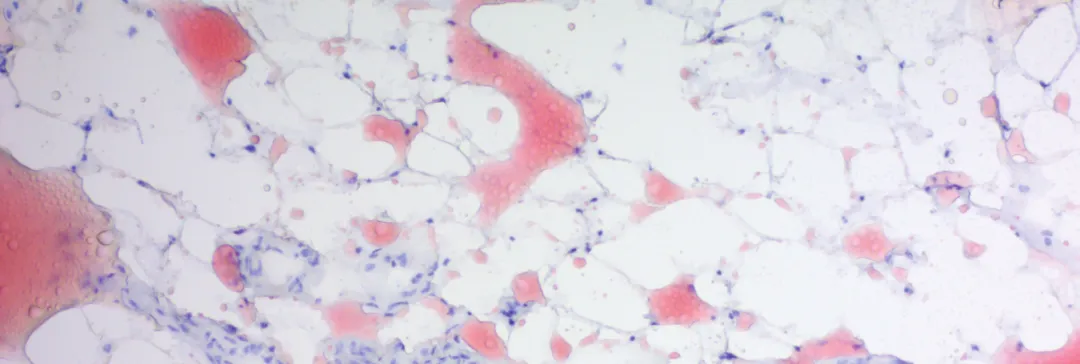

Orcein染色 (Orcein Stain)

染色特点

HBsAg:深红色/棕色

弹性纤维:深红/棕色

铜沉积物:深红色/棕色

背景:红/紫色的光

图 2. Orcein染色 Orcein Stain